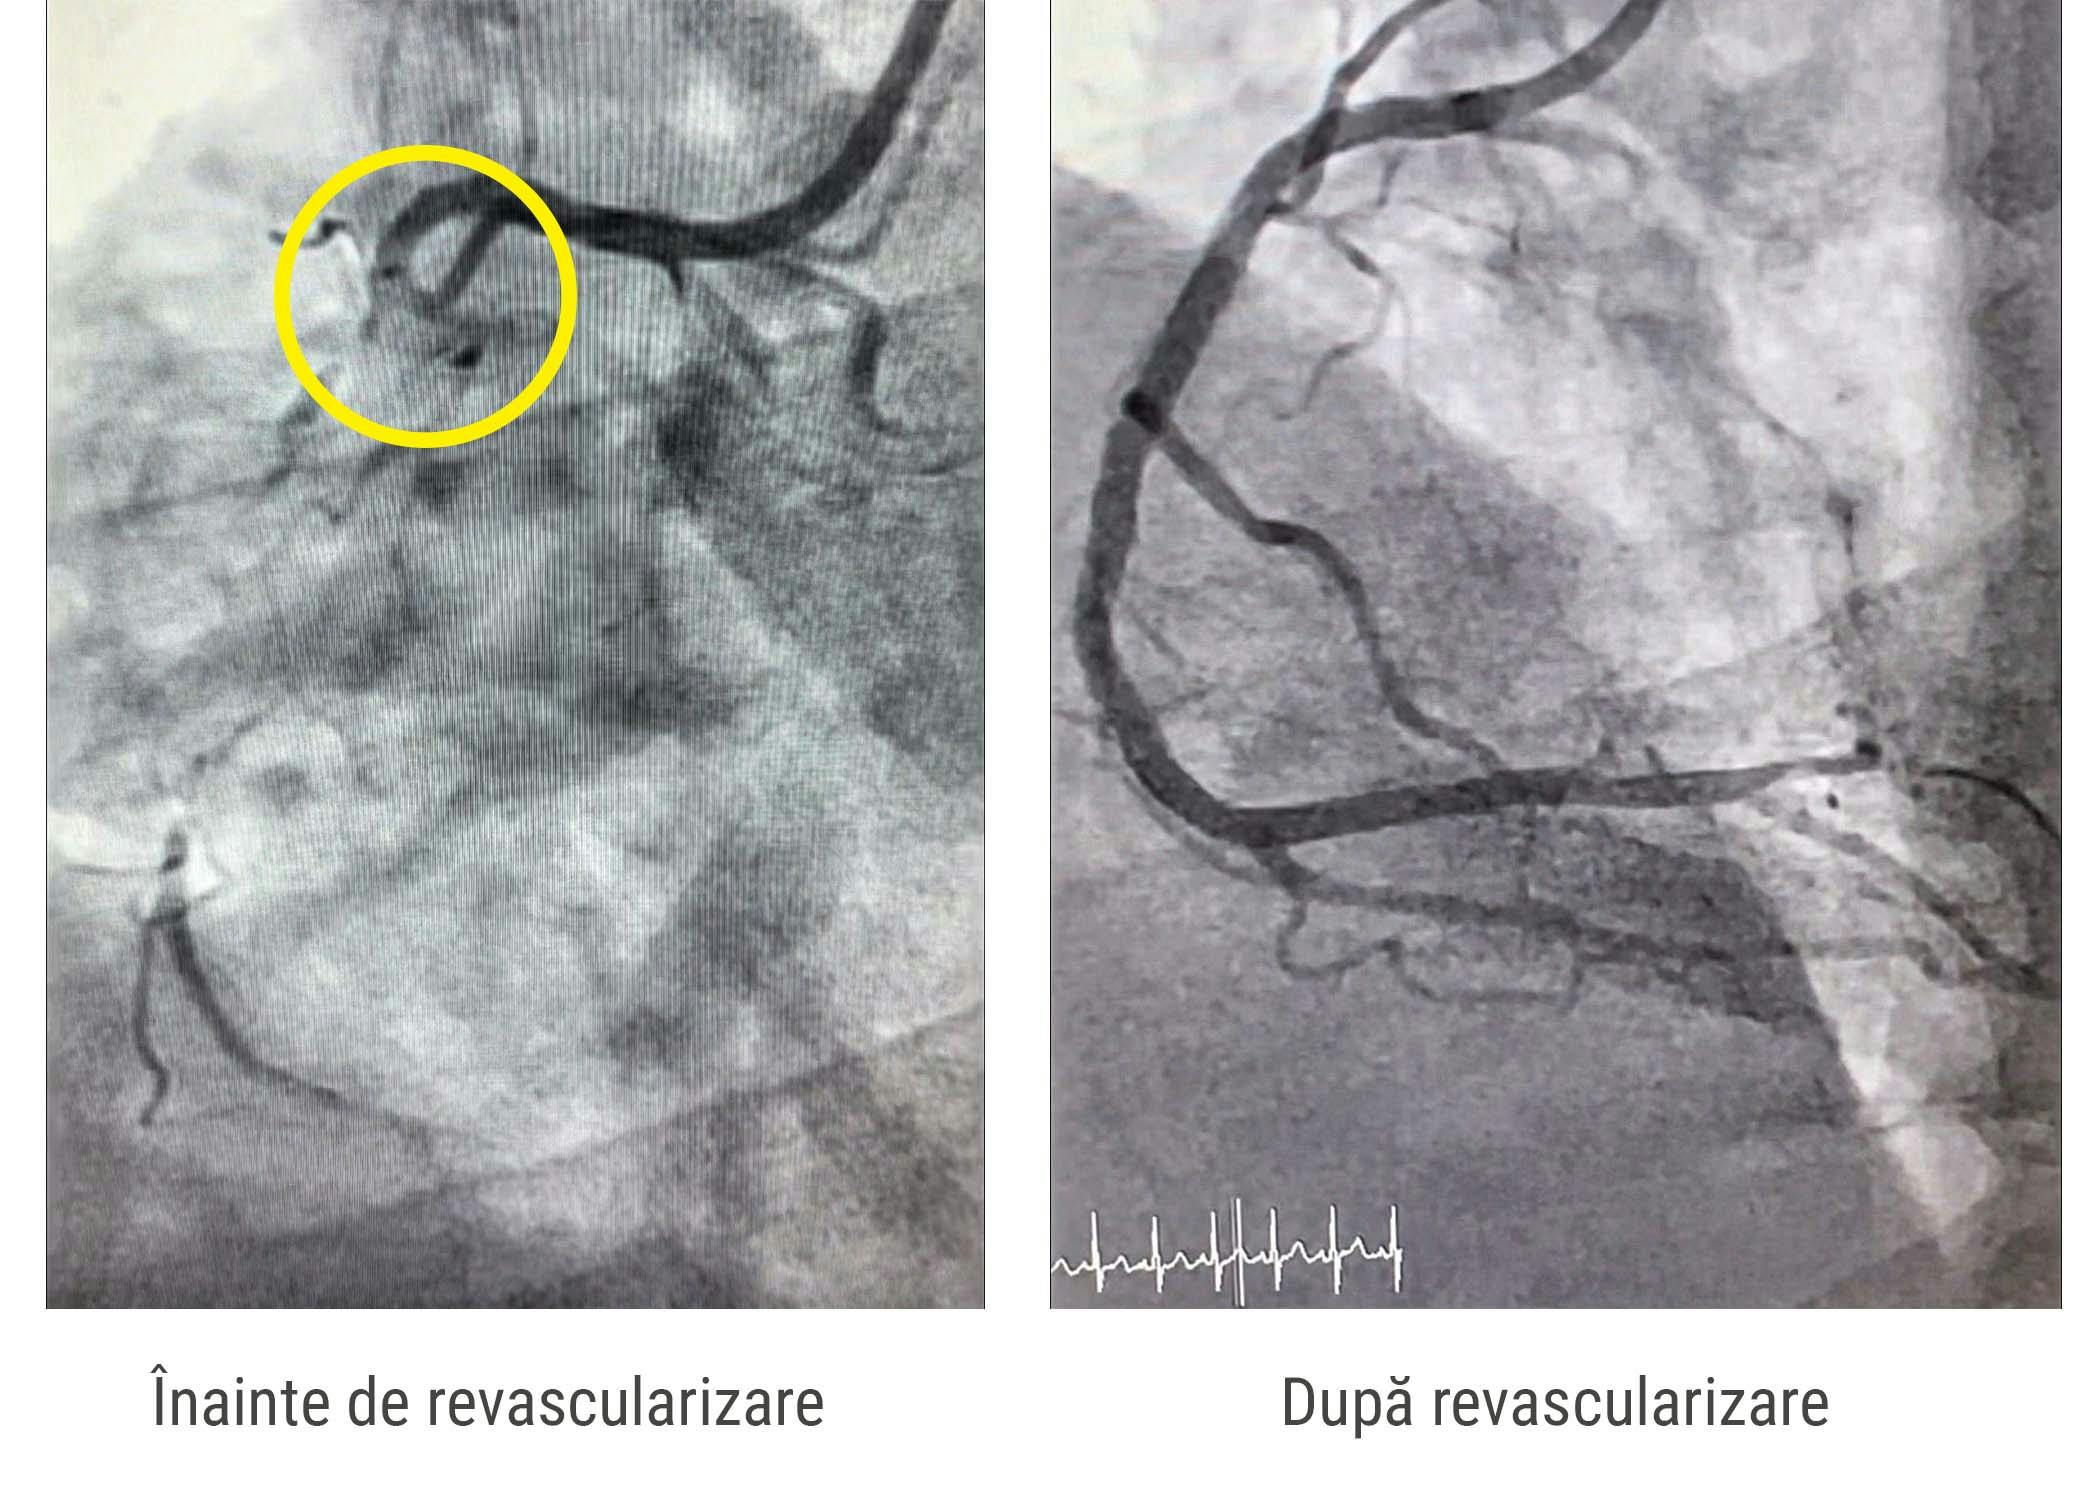

În contextul clinic marcat de agravarea insuficienței cardiace și de persistența anginei pectorale la efort, medicul cardiolog curant a decis să trimită pacientul în centrul MONZA ARES din Constanța, pentru evaluare și tratament. Coronarografia efectuată de dr. Adnan Mustafa, medic cardiolog intervenționist, a arătat că una dintre principalele artere de la inima prezintă o ocluzie cronică. Sub dovada imagistică a ischemiei miocardice importante în teritoriul acestei artere se decide revascularizarea arterei prin tehnica minim invazivă.

Procedura a fost realizată cu succes de către Dr. Adnan Mustafa, medic cardiolog intervenționist, prin utilizarea unei tehnici de intubare selectivă cu cateter ghid J.R. 4, care a permis avansarea a două ghiduri de înaltă precizie: Pilot 150 și Hi-Torque Floppy II Extra Support, acestea fiind introduse până la extremitatea distală a arterei afectate. Pentru a facilita deschiderea treptată a vasului coronarian, s-au efectuat dilatări repetate folosind baloane de diferite dimensiuni (Mini Trek 1.2/20 mm, 2.0/20 mm și Trek 3.0/30 mm). În final, s-au implantat cu succes trei stenturi Xience Pro S, realizând astfel revascularizarea completă a arterei coronariene ocluzionate.

Această intervenție complexă a permis restabilirea fluxului sangvin corespunzător în zona afectată, cu un impact semnificativ asupra ameliorării stării clinice a pacientului. Astfel, s-a obținut o îmbunătățire a calității vieții și o reducere a simptomelor de angină pectorală, contribuind la prevenirea unor complicații cardiovasculare suplimentare. Pacientul a fost externat a doua zi după intervenție în stare bună, fără simptomatologia inițială și cu recomandări medicale ce țin de modificarea stilului de viață și revenirea la controale cardiologice regulate.